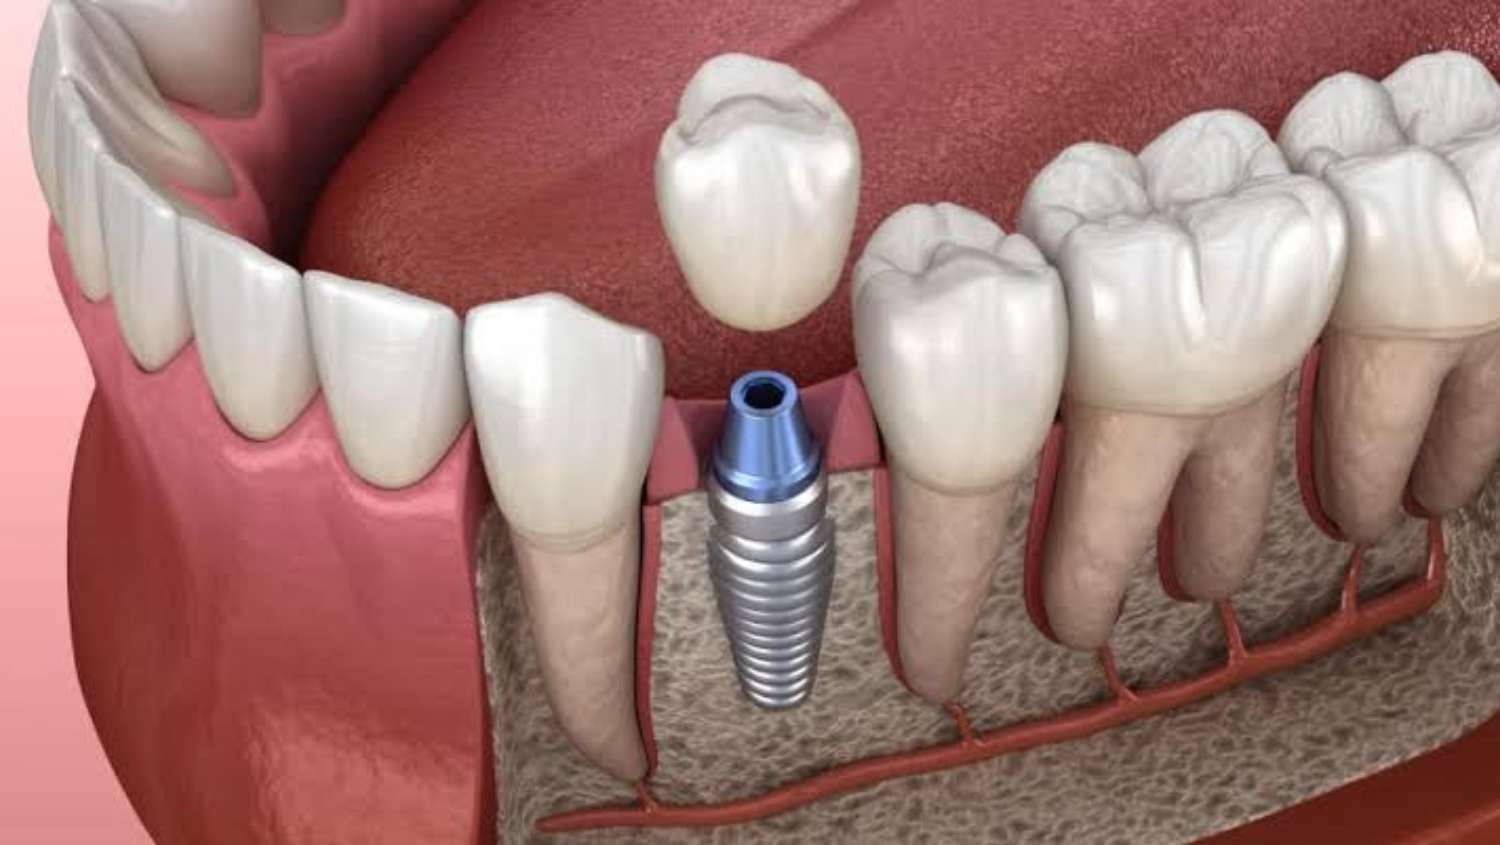

¿Qué es un implante dental?

Los implantes dentales son raíces dentales artificiales hechas de titanio. Al igual que una prótesis de rodilla o cadera, se integran con la anatomía circundante para reemplazar la parte de su cuerpo que se perdió o dañó, en este caso, con el hueso alveolar, con el fin de mejorar su salud y calidad de vida, pudiendo reemplazar un solo o varios dientes faltantes.

La colocación del Implante Dental se realiza a través de una sencilla y rápida cirugía ambulatoria con anestesia local. Una vez colocado el Implante es necesario esperar entre 3 a 6 meses para que se produzca el proceso biológico de osteointegración entre el implante y el hueso, esto le ofrecerá un base estable a la futura corona dental o prótesis dental.